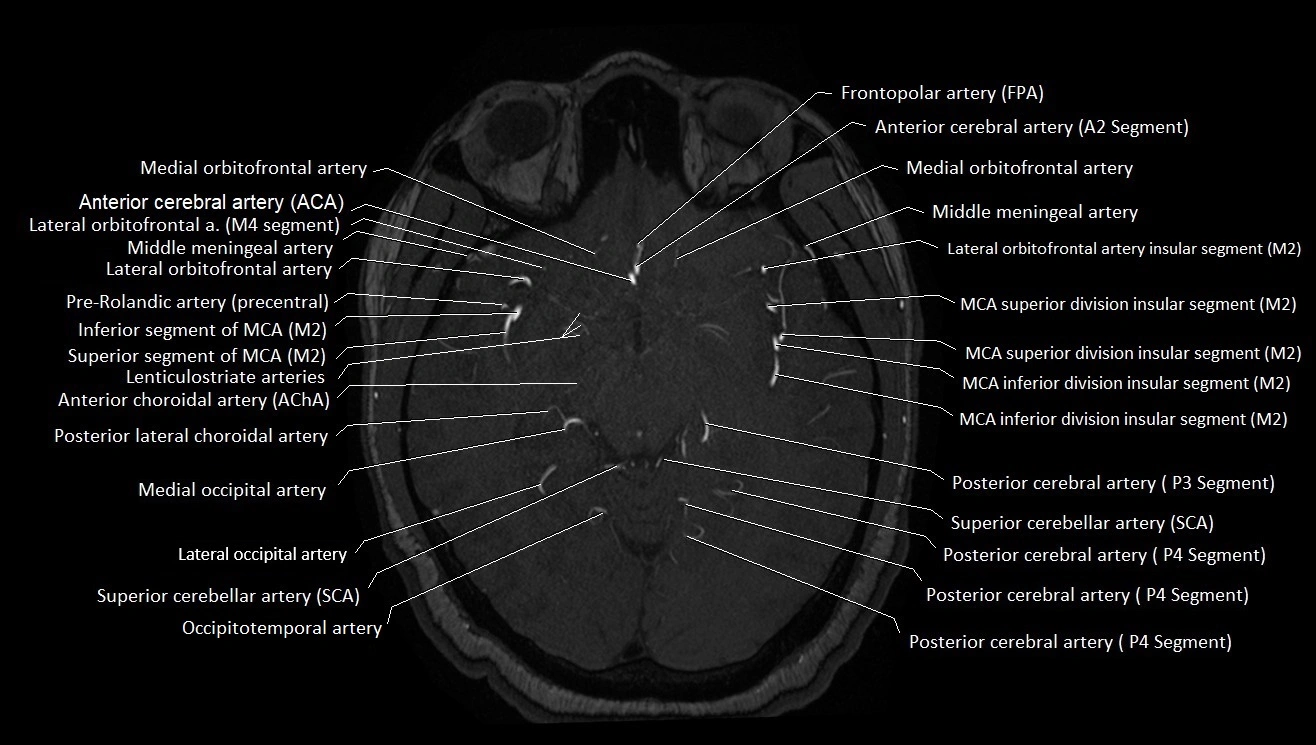

MRA (Magnetic Resonance Angiography):

• Flow-related enhancement makes the AChA appear as a bright, linear vascular signal against suppressed background

• High sensitivity for origin and proximal course; distal branches may be too small to resolve

• Detects stenosis, occlusion, aneurysm, AVM feeders

MRI images

image